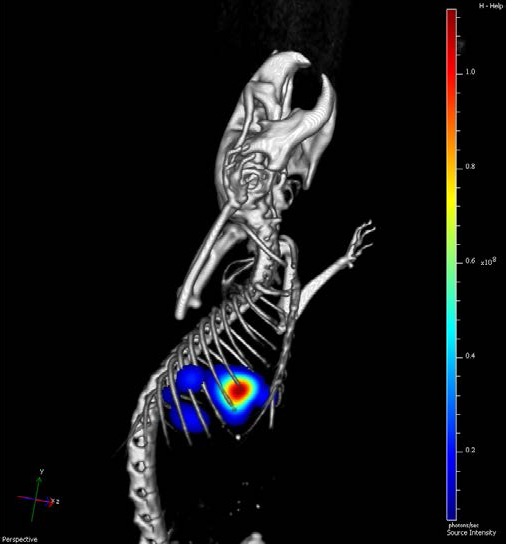

マイクロCTを他のモダリティと組み合わせることで、生体の健康状態や疾患の構造的・機能的理解が深まります。

GX IIIは、専用のマウスイメージングシャトル(MIS)を用いて、マイクロCTデータとIVIS Imaging Systemのデータをシームレスに統合可能です。シャトルは両プラットフォームに容易に装着でき、撮影中の位置再現性を維持します。

基準マーカー機能により、数クリックで自動データ融合を実現。取得データはDICOM形式でエクスポートでき、各種解析ソフトウェアで利用できます。

図12. マウスの肺に移植されたIVISense腫瘍細胞株のIVIS Spectrumによる光イメージングとGX IIIによるCT画像の融合